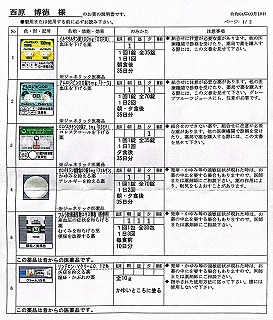

レボセチリジン塩酸塩錠5mg「武田テバ」 モンテルカスト錠10mg「トーワ」

2021.04.24 2021.03.06 中垣医院処方箋 =PDF

62:防風通聖散=膨満感対応 68:芍薬甘草湯=こむら返り対策